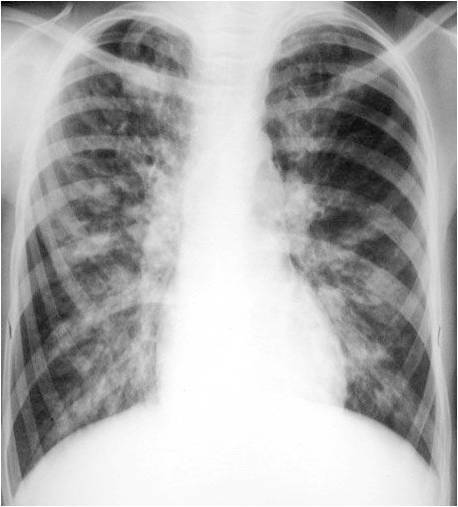

What does this image depict?

bronchiectasis

What does this CXR depict?